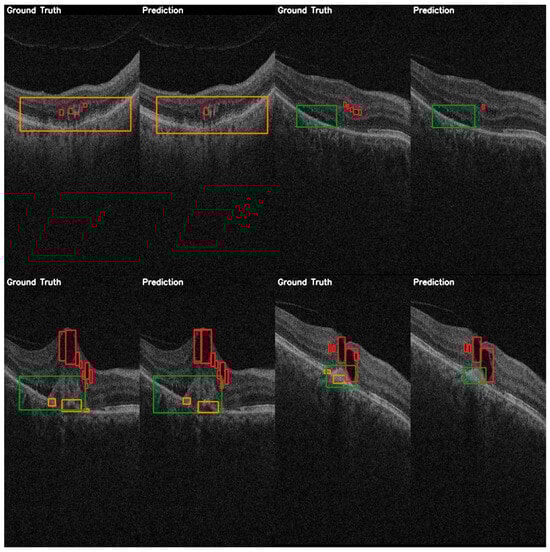

3.1. Performance Analysis of YOLO Versions on the AROI Dataset

3.2. Performance Analysis of YOLO Versions on the OCT5k Dataset